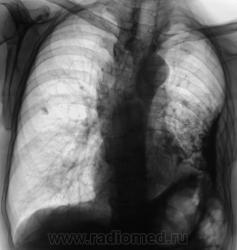

• https://radiomed.ru/sites/default/files/styles/case_slider_image/public/user/12/104.Dela_._1.jpg?itok=Onhwl3Zg

Какие мнения?